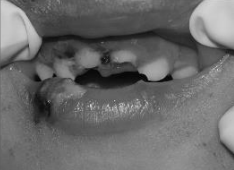

Observe a imagem a seguir:

Sobre os traumas dentários, a imagem INDICA: